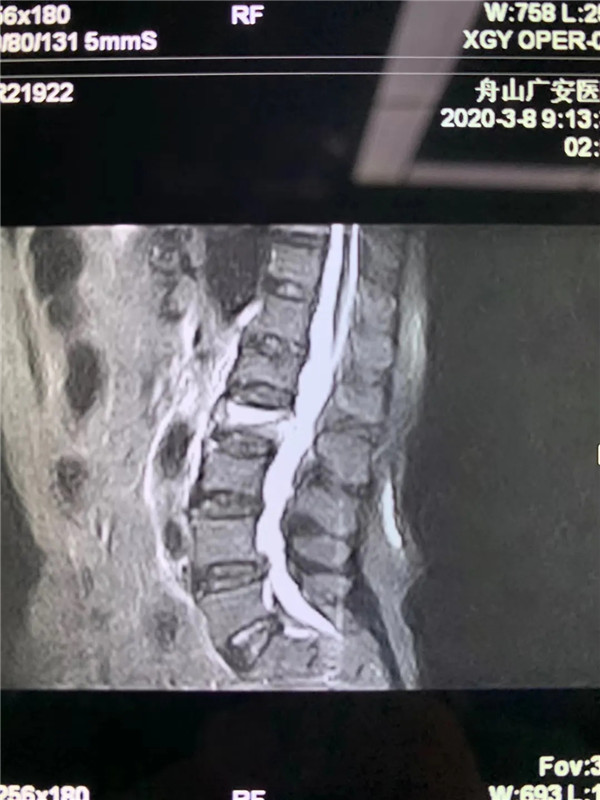

經(jīng)過仔細問診和查體后,初步診斷曹阿姨是椎體壓縮骨折了,在完善胸腰椎的MRI線檢查后,也證實了推斷。在與曹阿姨及家屬充分溝通后,戈才華主任為曹阿姨實施了微創(chuàng)手術,很快為其緩解了疼痛。

(MRI顯示椎體壓縮性骨折)